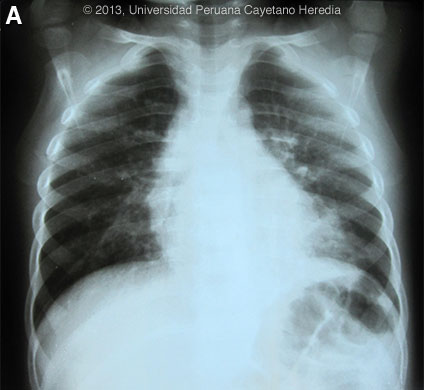

The following patient was seen at the Regional Hospital of Loreto in Iquitos. ![]() ![]() History: Previously healthy 2 year 10 month old male presents with a 2-week history of dry cough. The mother states that over the 2 weeks, the cough became paroxysmal with most of the events lasting up to a maximum of 5 minutes [see Video at right]. Between episodes the child was active with no pain. On the day of admission the child developed inspiratory stridor during the episodes of cough and developed an unquantified fever. In addition, he was less active and not playing as usual, with some diminution of oral intake. Mother denies any rhinorrhea, cyanosis or vomiting. Epidemiology: Born and raised in urbanized areas of Iquitos in the Peruvian Amazon. Lives with 4 siblings and parents all of whom are well. No known ill contacts. Does not attend a day-care center. Vaccinations completed up to 1 year of age, including hepatitis B, yellow fever, and MMR. Physical Examination (on admission): Afebrile, HR: 92, RR: 30. No acute distress. No pallor; capillary refill <2s. HEENT: Pharynx normal, no lymphadenopathy. Chest: lung fields clear. CVS: S1, S2 normal; no murmurs. Abdomen: normal bowel sounds, soft, no hepatosplenomegaly. Neurological: alert, following commands. Laboratory Results: Hb: 11.2. Hct: 34.3. WBC: 36,900 (neu: 37%, eos: 4%, mono: 1%, lymph: 58%); Platelets: 375,000. CXR is Image A.

Discussion: PCR of pharyngeal secretions performed by the US NAMRU-6 in Lima was positive for Bordetella pertussis. Diagnosis is historically based on culturing B. pertussis, a small, fastidious Gram-negative coccobacillus with exclusive affinity for the mucosal layers of the human respiratory tract, from nasopharyngeal specimens obtained during the catarrhal stage and early paroxysmal stage (<2 weeks from onset). However, culture is highly specific but not very sensitive, and requires special culture media. PCR is clearly more sensitive when feasible, is useful up to 4 weeks after onset (including up to 7 days after antibiotics started) and is currently most widely used in resource rich settings. Serological diagnosis requires paired serum specimens collected one month apart, so is not useful clinically. High antibody concentrations in single sera from unvaccinated individuals suggest recent infection. During the first year following vaccination, serological testing using a single serum sample is problematic. Pertussis is a highly infectious disease with an incubation period of 9–10 days (range, 6–20 days), transmitted via the respiratory droplet route. Estimates from WHO suggest that in 2008 about 16 million cases of pertussis occurred worldwide, 95% of which were in developing countries, and that about 195,000 children died from this disease. In the early catarrhal stage, it has a secondary attack rate of up to 90% among non-immune household contacts. Untreated patients may be contagious for 3 weeks or more, although transmission diminishes rapidly after the catarrhal stage. Chronic carriers of B. pertussis are uncommon. Natural infection confers some limited immunity, especially when boosted by frequent re-exposure to B. pertussis. However, long-lasting natural immunity cannot be ensured and should not be presumed. The onset of disease is marked by non-specific catarrhal symptoms without fever. In typical cases an intermittent cough becomes paroxysmal after 1–2 weeks, typically ending with an inspiratory whoop. Whooping is characterized by the noise of the forced inspiratory effort but is not always present, especially in infants <3 months. Post-tussive emesis occurs frequently. Paroxysms can develop spontaneously or be precipitated by external stimuli. Symptoms are often worse at night, and can last from 2–6 weeks. Milder symptoms without the typical whoop may be observed in individuals who have previously been vaccinated, and older children and adolescents. In young infants, pertussis may cause apnea, bradycardia, and cyanosis without cough or whooping, whereas in adolescents and adults persistent cough may be the only manifestation. The differential diagnosis of pertussis includes RSV (respiratory syncitial virus), mycoplasma, adenoviruses and Chlamydia trachomatis. A characteristic though not constant nonspecific laboratory indication of B. pertussis infection is an absolute lymphocyte count over 10,000 lymphocytes per microlitre (21,400 in the case here). Marked leukocytosis (e.g., >60,000 cells/microlitre) has been associated with increased pertussis severity. Chest radiographs may show perihilar infiltrates and atelactasis but a consolidation should raise the suspicion of a bacterial super-infection. Pneumonia is one of the most frequent complications of pertussis with an incidence of approximately 6%, with higher rates in infants less than 6 months. Pneumonia may be a primary manifestation of B. pertussis infection or the result of secondary bacterial infection. In developing countries, the case-fatality rate for pertussis is estimated at 4% in infants aged <1 year and at 1% in children aged 1–4 years. Pertussis is a clinical diagnosis and a clinical case can be defined as an acute cough illness lasting at least 14 days accompanied by one of the following: 1) paroxysms of coughing; 2) inspiratory whoop; or 3) post-tussive vomiting. In an outbreak or following a household contact to a known case, a clinical case is defined as a cough illness for at least 14 days; presence of the typical pertussis-associated features is not required. Young infants are more likely to need hospitalization than are older children or adults and the majority under 6 months of age require hospitalization. Indications include: 1) respiratory distress; 2) evidence of pneumonia; 3) inability to feed; 4) cyanosis or apnea; 5) seizures; or 6) age <3 months. Minimum criteria for discharge include all of the following: 1) no hypoxia or bradycardia after a coughing paroxysm; 2) can feed adequately; 3) reliable care at home; 4) available outpatient follow-up. Pertussis vaccine (combined with diphtheria toxoid and tetanus toxoid) has been part of WHO’s Expanded Programme on Immunization since its inception and in 2008 about 82% of all infants worldwide received 3 doses of pertussis vaccine during the first 6 months of life. WHO recommends a 4th dose in the second year of life where possible. Perú still uses the whole cell pertussis vaccine and this child had received only the initial 3 doses despite a 4th dose being recommended according to the national program. Little data exists on the duration of protection following pertussis vaccination in developing countries. Several studies in the industrialized world show that protection wanes after 4–12 years. The child received azithromycin for 5 days for treatment of pertussis and ceftriaxone for the possibility of a non-pertussis secondary pneumonia noted clinically and on chest x-ray. Azithromycin is the sole agent of choice in infants less than 1 month and erythromycin, clarithromycin and TMP-SMX (in those >2 months) are possible options otherwise. The same azithromycin regimen is used both for treatment and prophylaxis. Treatment does not affect clinical course but stops transmission. The American Academy of Pediatrics recommends antimicrobial prophylaxis for all close contacts, such as childcare workers or household members, regardless of their immunization status. Pertussis immunization should be initiated or completed in close contacts who are not properly immunized. The utility of post-exposure antibiotic prophylaxis after 21 days of onset of cough in the index case is unclear. Children with pertussis or suspected pertussis may return to school or day care after they have completed 5 days of effective antimicrobial therapy or, if they are not treated, 21 days after the onset of symptoms. See Pediatr Rev. 2012 Sep;33(9):412-20 doi: 10.1542/pir.33-9-412 for a recent review of pertussis in children. Thanks to attending physician Dr. Camilo Ruiz, Pediatric Intensivist at the Regional Hospital of Loreto in Iquitos, and to Dr. Nicolás Barrós and Dr. Myriam Perreault-Samson for collation and comments on the case presentation.